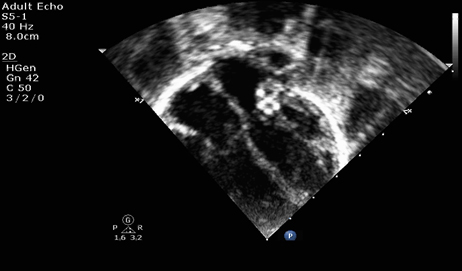

梅*,37岁,G2P1,孕27周首诊,分别于31周、35周随访 ,胎儿心彩超诊断:左冠状动脉右房瘘、右房右室增大、冠状窦增大、少量心包积液。孕35+3周剖宫产一男婴,出生体重2750g,生后心彩超诊断:左冠状动脉-右房瘘、动脉导管未闭、肺动脉高压 。生后立即送入NICU监护,立即予心彩超检查,生后第5天予左冠状动脉-右房瘘介入封堵术,即使用介入的方法将封堵器放置于心房的瘘口处。手术成功,患儿瘘口处无分流。